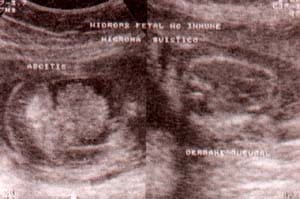

fig. 59. – (a). hallazgos ecográficos en feto con síndrome de turner. gran higroma quístico. característico de esta alteración cromosómica.alformaciones fetales fig. 59. – (b). hidrops fetal secundario, se observa ascitis y derrame pleural.